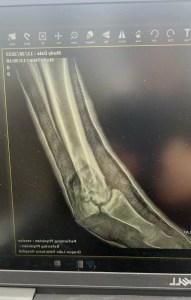

While traditional equine medical care might see injuries like hers as insurmountable, this filly’s tenacious spirit was a testament to an animal’s engrained will to survive. By the time she was discovered with her injury, she was facing:

- A severe and rapidly-spreading infection.

- A complex fracture of her cannon bone with severe soft tissue damage.

On day one under the surgeons care it was determined the little foals leg could likely be saved. The next 3 months in Cody, Wyoming were touch and go as the team at Yellowstone Equine Hospital controlled the infection and set Second Chance’s bones to fuse. It was a miracle in and of itself, but that was only the beginning. The rest of Second Chance’s healing journey was dependent on the care she would receive post Yellowstone. Now she needed to come home and settle in to beat the harsh Canadian winter.

While at Dragon Lake Vet, Second Chance has made fantastic progress. She gets stellar around the clock care including supplements, training and cast changes. When she exhibits healing to a point where she can full weight bear on her hoof and leg without a hard cast, she’ll be able to come home and reunite with her dam, Juno. We think we are close. But we still have to be set up at the ranch to X-ray, change casts and dressings to be able to properly care and support her

You and your family willingness to fight as long as Second Chance will to continued fighting. The xrays tell the store, the truth. Most would have ended it all. To spend the time making phone calls, asking questions, then traveling for days to safely transport her and her mom to Wyoming. Vet’s that were also willing to take on the challenge. Above and beyond, I am not sure you know any other way, to be honest. Second Chance looks unbelievable beautiful, strong and even after all that she has been through you can still see the fight in her sweet soft eyes. When you are around her…. she know you are her Hero and she shows you her love in her behavior around you.